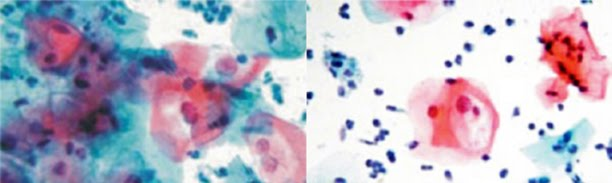

Coloração de Papanicolaou:

O método de Papanicolaou utiliza um conjunto de corantes e tem como objetivo a evidenciação das variáveis na morfologia e dos graus de maturidade e de atividade metabólica celular.

Esse método se baseia nas ações de um corante básico (com afinidade pelo núcleo das células: a hematoxilina), um corante ácido (que se combina com o citoplasma das células queratinizadas: orange G) e um corante policromático (que oferece tonalidades de cores diferentes no citoplasma das células: EA-65).

Hidratação: esta etapa requer a reposição gradual da água das células por meio de banhos alcoólicos de concentrações decrescentes até a água destilada.

Coloração nuclear: as células hidratadas podem agora receber um corante aquoso para corar os núcleos (hematoxilina de Harris).

Desidratação: para receber corantes alcoólicos citoplasmáticos, devemos agora retirar a água das células com banhos alcoólicos de concentrações crescentes.

Coloração citoplasmática: nesta etapa, o citoplasma das células é corado pelos corantes orange G e EA-65, de modo a diferenciar com diversas tonalidades o citoplasma das células de acordo com a sua maturidade e metabolismo.

Desidratação, clarificação e selagem: a água agora deve ser retirada com concentrações alcoólicas crescentes, clarificadas e seladas com meios permanentes hidrofóbicos.